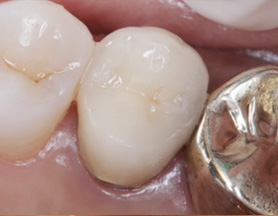

염증을 제거하는 신경치료 후 치근단 부위가 빠르게 회복되어 깔끔하게 신경치료를 완료하고 크라운 보철물을 씌웠습니다. 신경치료를 받은 치아는 약해져 있기 때문에 크라운 보철물로 씌워주어 세균 감염을 예방해야 합니다.

신경치료를 받은 치아는 수분이나 영양공급이 이루어지지 않기 때문에 쉽게 치아가 부서지거나 깨질 수 있으므로,반드시 신경치료 한 치아는 크라운을 씌워 치아를 보호해 주어야 합니다.